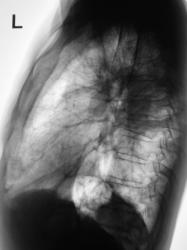

Начало 2008 года. При расшифровке цифровых флюорограмм пациент "взят на контроль", дообследован.

Конец 2008 г. При расшифровке цифровых влюорограмм пациент повторно взят на контроль и дообследован

Сегодня пациент прислан на рентгенологическое исследование органов грудной полости

Грустно и к сожалению довольно обычно, чаще всего пропускается s6 слева. Очень хочется знать, что подразумевается под "взят на контроль и дообследован"? Потому что изменения в левом корне, позволяющие заподозрить заболевание видны на первых снимках. Кроме того дообследуйте грудной отдел позвоночника - значительно снижена высота грудного позволка на уровне ателектаза.

Дообследование (первое) заключалось в рентгенографии в прямой и боковой проекциях, линейной томографии. Кстати, весьма хорошо "размазали" левый корень и направили в областной ОД. Кстати, тогда в грудных позвонках еще секундарных изменения не было.

В той, о которой я говорил - "Данных за онкологический процесс нет". Рекомендовано то - то и то - то и рентген-контроль через 3 месяца. Самое плохое, что и пациент успокоился, да и участковый терапевт (в конце года), с учетом появления субфебрилитета направил не на рентгенологическое исследование, а на флюорографию. Взяли на контроль, опять дообследовали, но уже в большем объёме, произвели и томографию позвоночника - на боковой рентгенограмме "визуализировалась порозность", ну а на томограммах ....

Послали повторно в ОД, коллеги с диагнозом согласились. Сегодня, когда обследовали пациента, я его просто не узнал - постарел лет на 10 (за год).